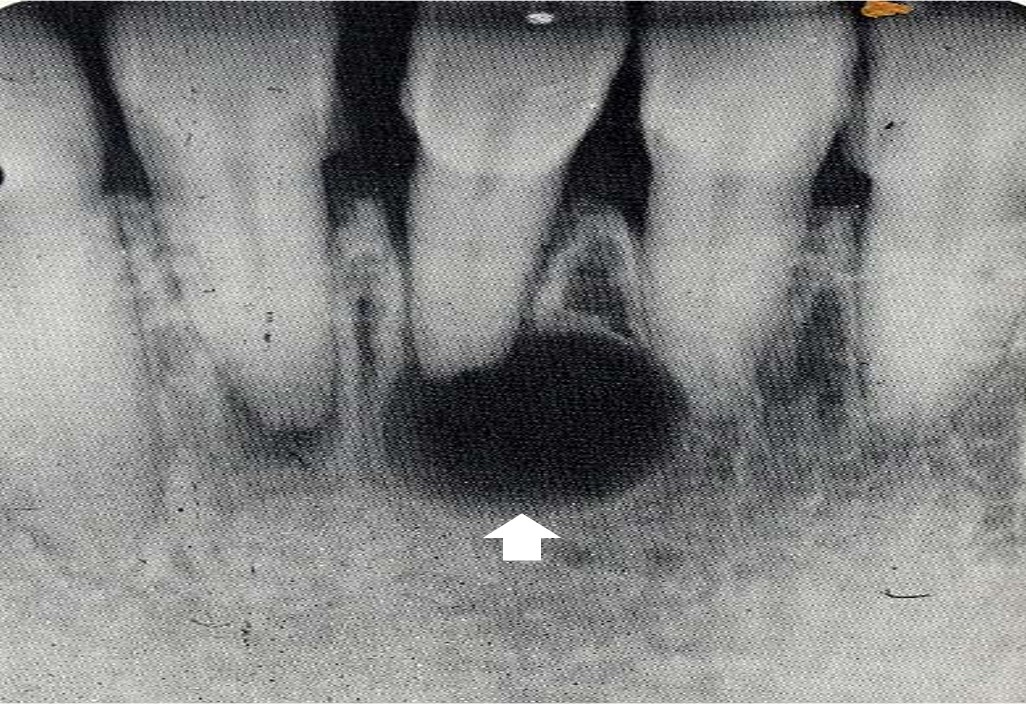

多见于20~49岁,男性多见,60%发生于上颌,以上颌切牙和单尖牙最为多见,伴有死髓牙,X线显示圆形或卵圆形透射区,边缘整齐,界限清晰(图13.1-13)。

图13.1-13 根尖周囊肿(X线)